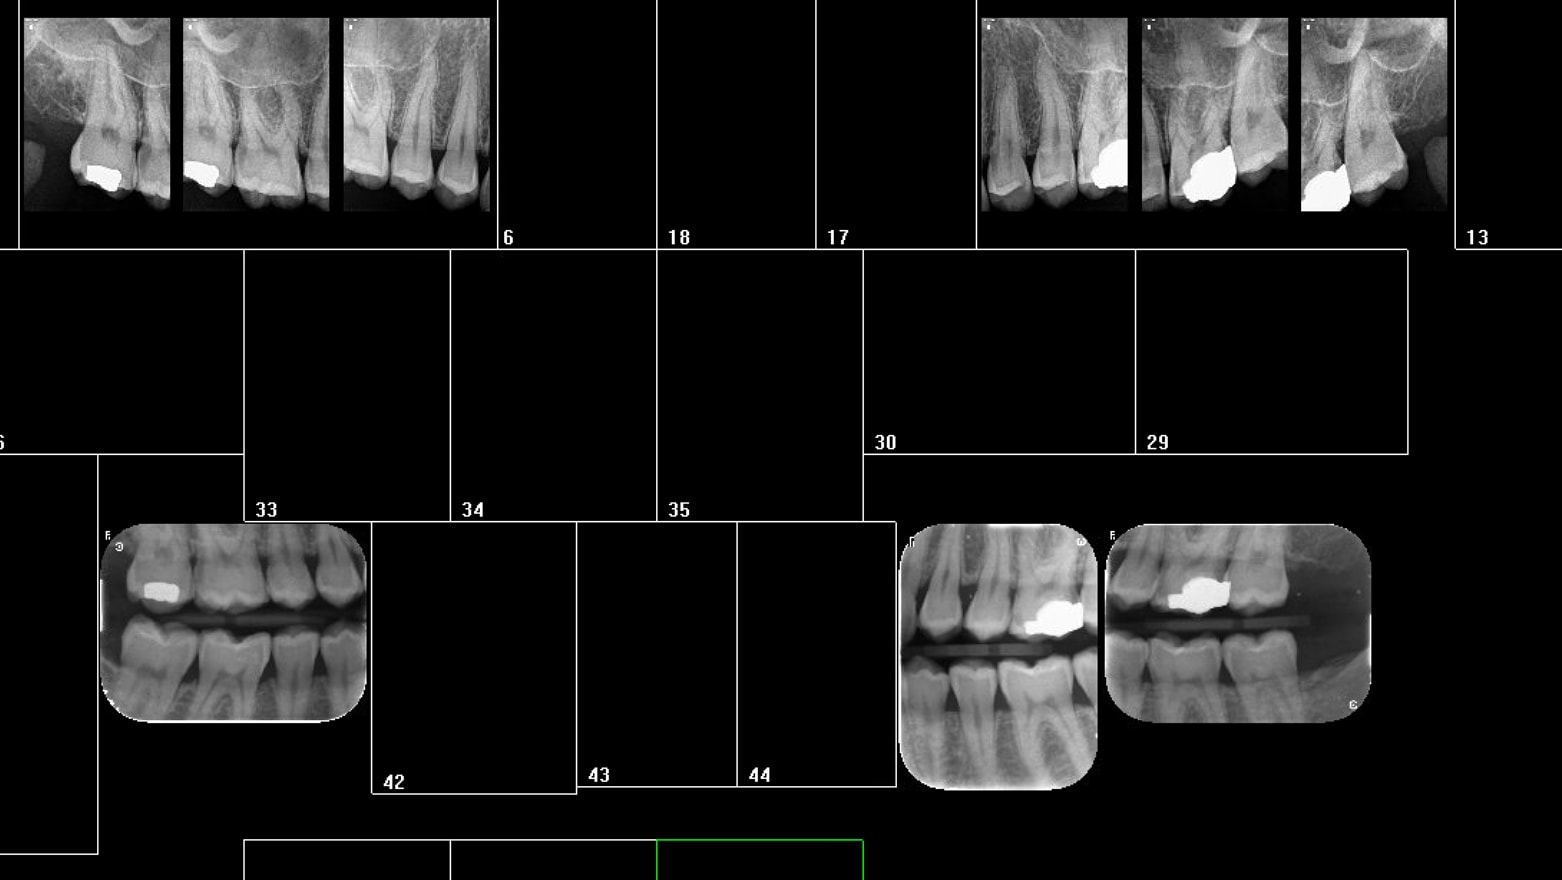

Petit quizz: capteur ou plaque phosphore ?

Capteur ou plaque phosphore qifvfv - Eugenol